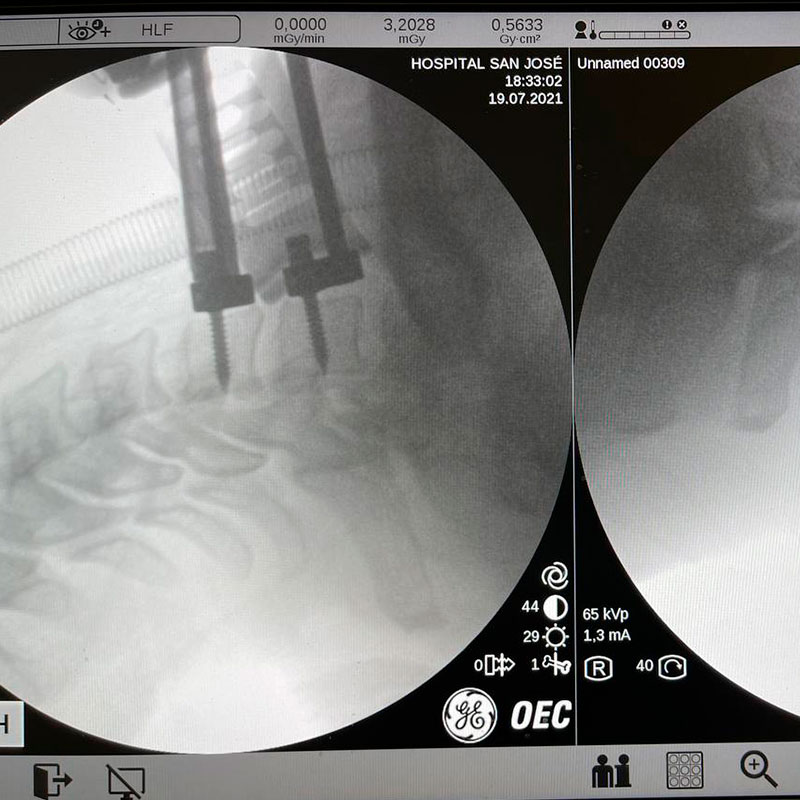

El abordaje es de apenas 2 centímetros con una apertura mínima, llegando al cuerpo vertebral mediante fluoroscopia y navegación.

Se llega al disco dañado por la parte anterior y se extrae, procediendo después a quitar la hernia por la parte posterior.Una vez observamos que los nervios están liberados, implantamos la prótesis móvil.